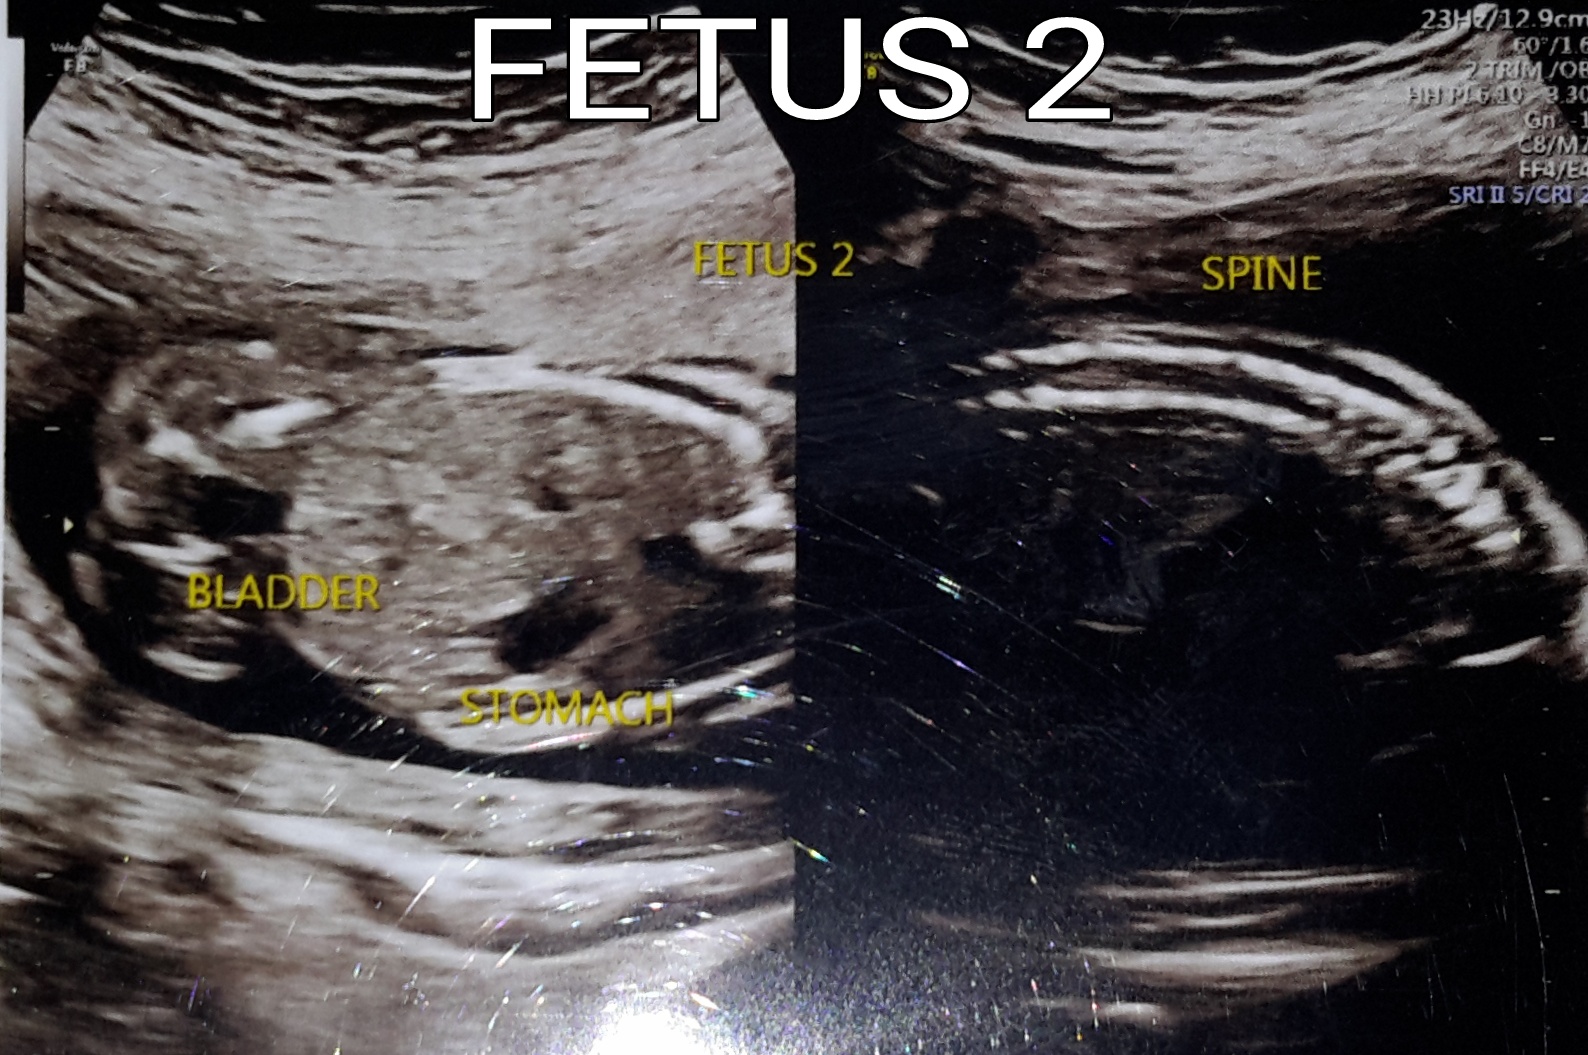

Here we go. 12 weeks ultrasounds

Attachment 40166

No nub on baby #1's pic but for baby #2 I see a bit of the nub. Maybe boy? It's so hard to tell as baby is curled up and the nub looks a bit cut off at the end.